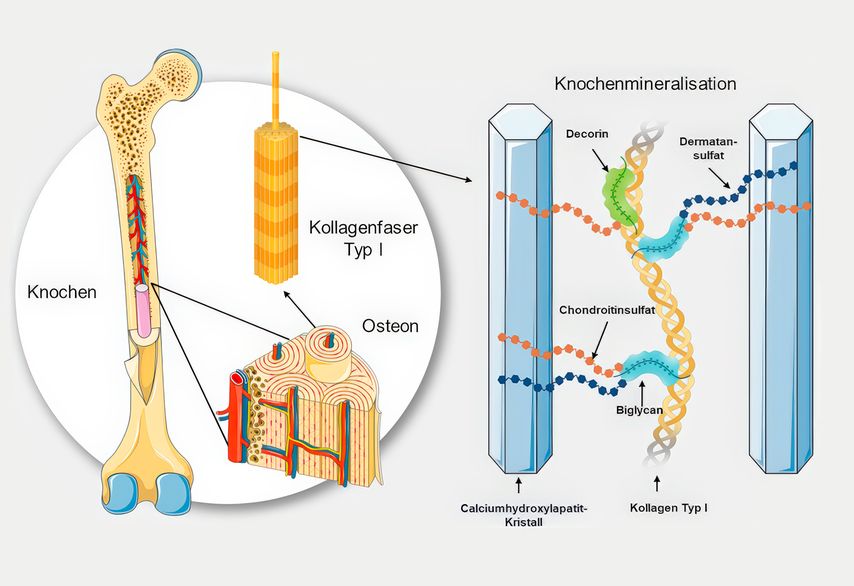

Der Knochen im Wandel

Mit zunehmendem Alter und insbesondere bei sinkendem Östrogenspiegel in den Wechseljahren kommen die Auf- und Abbauprozesse aus dem Gleichgewicht. Die Aktivität der Osteoklasten nimmt zu, während die Osteoblasten weniger effizient arbeiten. Dies führt zu einem Nettoverlust an Knochenmasse. Osteoblasten sind für die Produktion der kollagenbasierten Knochenmatrix sowie deren Mineralisation essenziell. Sie synthetisieren organische Komponenten wie Kollagen Typ I und Glykosaminoglykane, die als Gerüst für die Einlagerung von Kalzium dienen. Die freien Kalziumionen (Ca2+) binden dabei an negativ geladenes Chondroitin- und Dermatansulfat und werden in Form von Hydroxylapatitkristallen in die organische Matrix eingebettet (Abb.1). Erst durch die organischen Bausteine wird eine geordnete Mineralisation des Knochens möglich.

Abb. 1: Vernetzung im gesunden Knochen.1 Aus Osteoblasten freigesetzte GAGs verbinden Kollagen Typ I mit Kalziumphosphatkristallen (modifiziert nach Fladerer JP und Grollitsch S)1